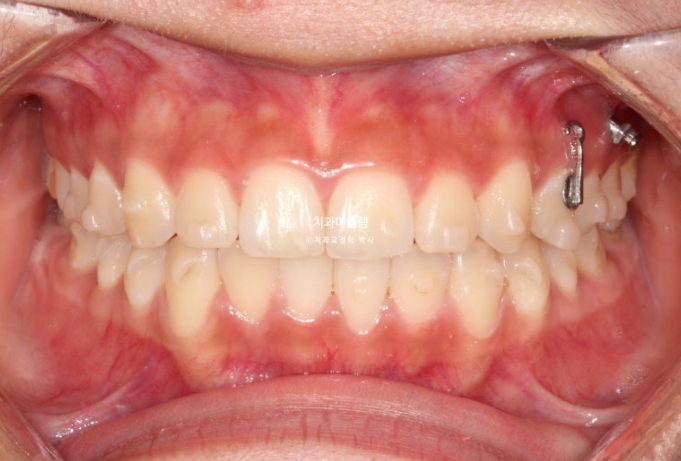

치료시작 11개월 차, 첫 세트의 48개 장치를 모두 낀 후 모습입니다.

중심선이 아직 약간 어긋나 있지만 덧니와 개방교합은 개선되었습니다.

좌측의 2급 교합이 아직 남아있습니다.

이 부분을 개선하고자 추가장치 제작에 들어갑니다.

재제작 추가장치 갯수는 10개입니다.